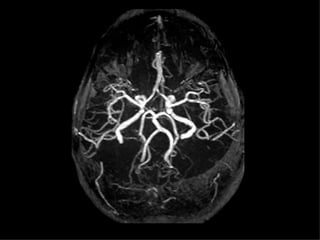

ACVh SA - Aneurismas

• La localización ampliamente preponderante de

los Aneurismas intracraneanos es en el polígono

de Willis, situado en la base del cráneo y dentro

de el:

– 33 % Complejo cerebral-comunicante anterior

– 33 % Sifón carotideo

– 33% Otras localizaciones

• Entre 15-20 % tienen aneurismas múltiples

• La principal causa de HSA es la rotura de un aneurisma

intracraneano

• Los aneurismas arteriales congénitos son dilataciones

debidas a ausencia congénita de la capa media y o

remanentes embriologicos, que por lo general son

pediculados y asientan en su mayoría en el polígono de

Willis

• Se considera que entre el 1 al 2% de la población poseen

esta malformación (autopsias); mientras que la incidencia

de Hemorragia subaracnoidea por aneurismas es de

10-20 pacientes por 100.000 habitantes y por año

• Predomina en la cuarta y quinta década de la vida, con

leve predominio del sexo femenino 3:2